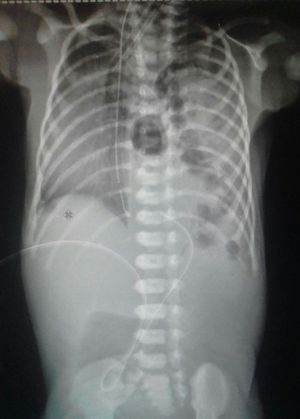

X-Rays to newborn

Bowels in the thoracic cavity π―

Diaphragmatic hernia...?